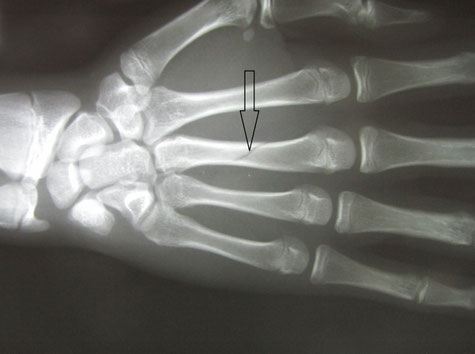

●右第3中手骨骨折

中学2年生 ラクビープレー中に骨折をしました。

当初、整形外科の診察を受けギプス固定をしてもらいましたが、

ボクシンググローブのような大きなもので、しかもギプスが皮膚を圧迫していたので当院に相談されました。

3週間後には大事な試合が待っています。

提携の整形外科で再度レントゲン検査をしてもらい転移(骨のずれ)がないことを確認し小さな固定にかえました。

毎日来院してもらい超音波治療とマッサージをしました。

2週経過した頃から圧痛(折れたところを押したときの痛み)は消失し、なんとか試合に間に合いました。

念のためさらに1週間来院してもらい治療を終了しました。